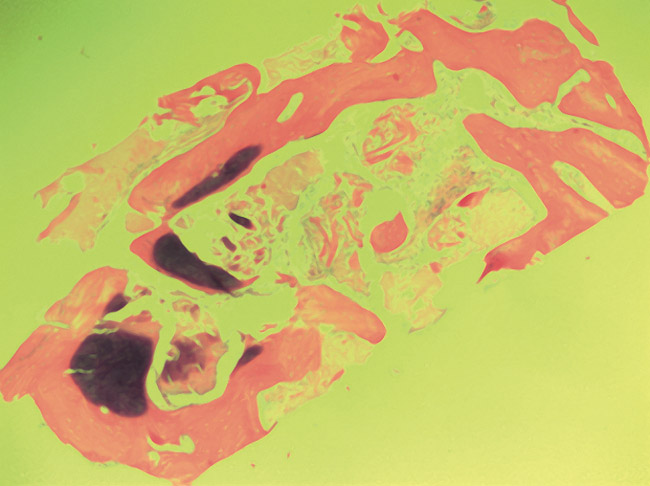

The restorative treatment plan encompassed tooth replacement in the first and second molar positions only, negating the need for the patient to incur the greater expense of augmenting the third molar site. Primary closure was achieved with a monofilament PTFE suture. Approximately 6 months after the extractions and augmentation procedure, the patient returned for implant placement surgery. Surgical reopening revealed excellent visual regeneration and ridge preservation (Figure 11). The site of the tooth No. 31 osteotomy was chosen for biopsy harvesting, because this is where the most severe bone loss existed at the time of extraction, and this site would be most representative of new bone formation, as opposed to possibly harvesting pre-existing native bone. This trephine core qualitatively revealed what was diagnosed by the histopathologist as "normal bone" without any foreign body or inflammatory responses being evident (Figure 12). Serving as a historic control, Trombelli et al reported on histomorphometric measurements of various tissues present at different time intervals. These authors describe great variability in human trephine cores taken from extraction sites. In relation to the present case series, Trombelli et al described the presence of a provisional matrix and woven bone dominating what they described as late-phase healing taken at 12 to 24 weeks after extractions. Although tissue modeling was described as fast, the authors found the remodeling of the newly formed bone to be what they called "seemingly slow." The trephine core presented in this particular case demonstrated this type of healing, as described by Trombelli et al.8 A high degree of woven bone as well as a cell and fiber-abundant provisional matrix was present.

It is also worth mentioning that although the retrieved trephine cores revealed qualitative evidence of healthy bone, without evidence of persisting graft material or adverse cellular reactions, histomorphometry was not performed. The percentages of woven bone, lamellar bone, and soft tissue within the cores were not evaluated. The purpose of the histologic component of this report is to demonstrate the presence of viable native bone, without undesired inflammatory processes or residual graft materials, in the locations of implant insertions.